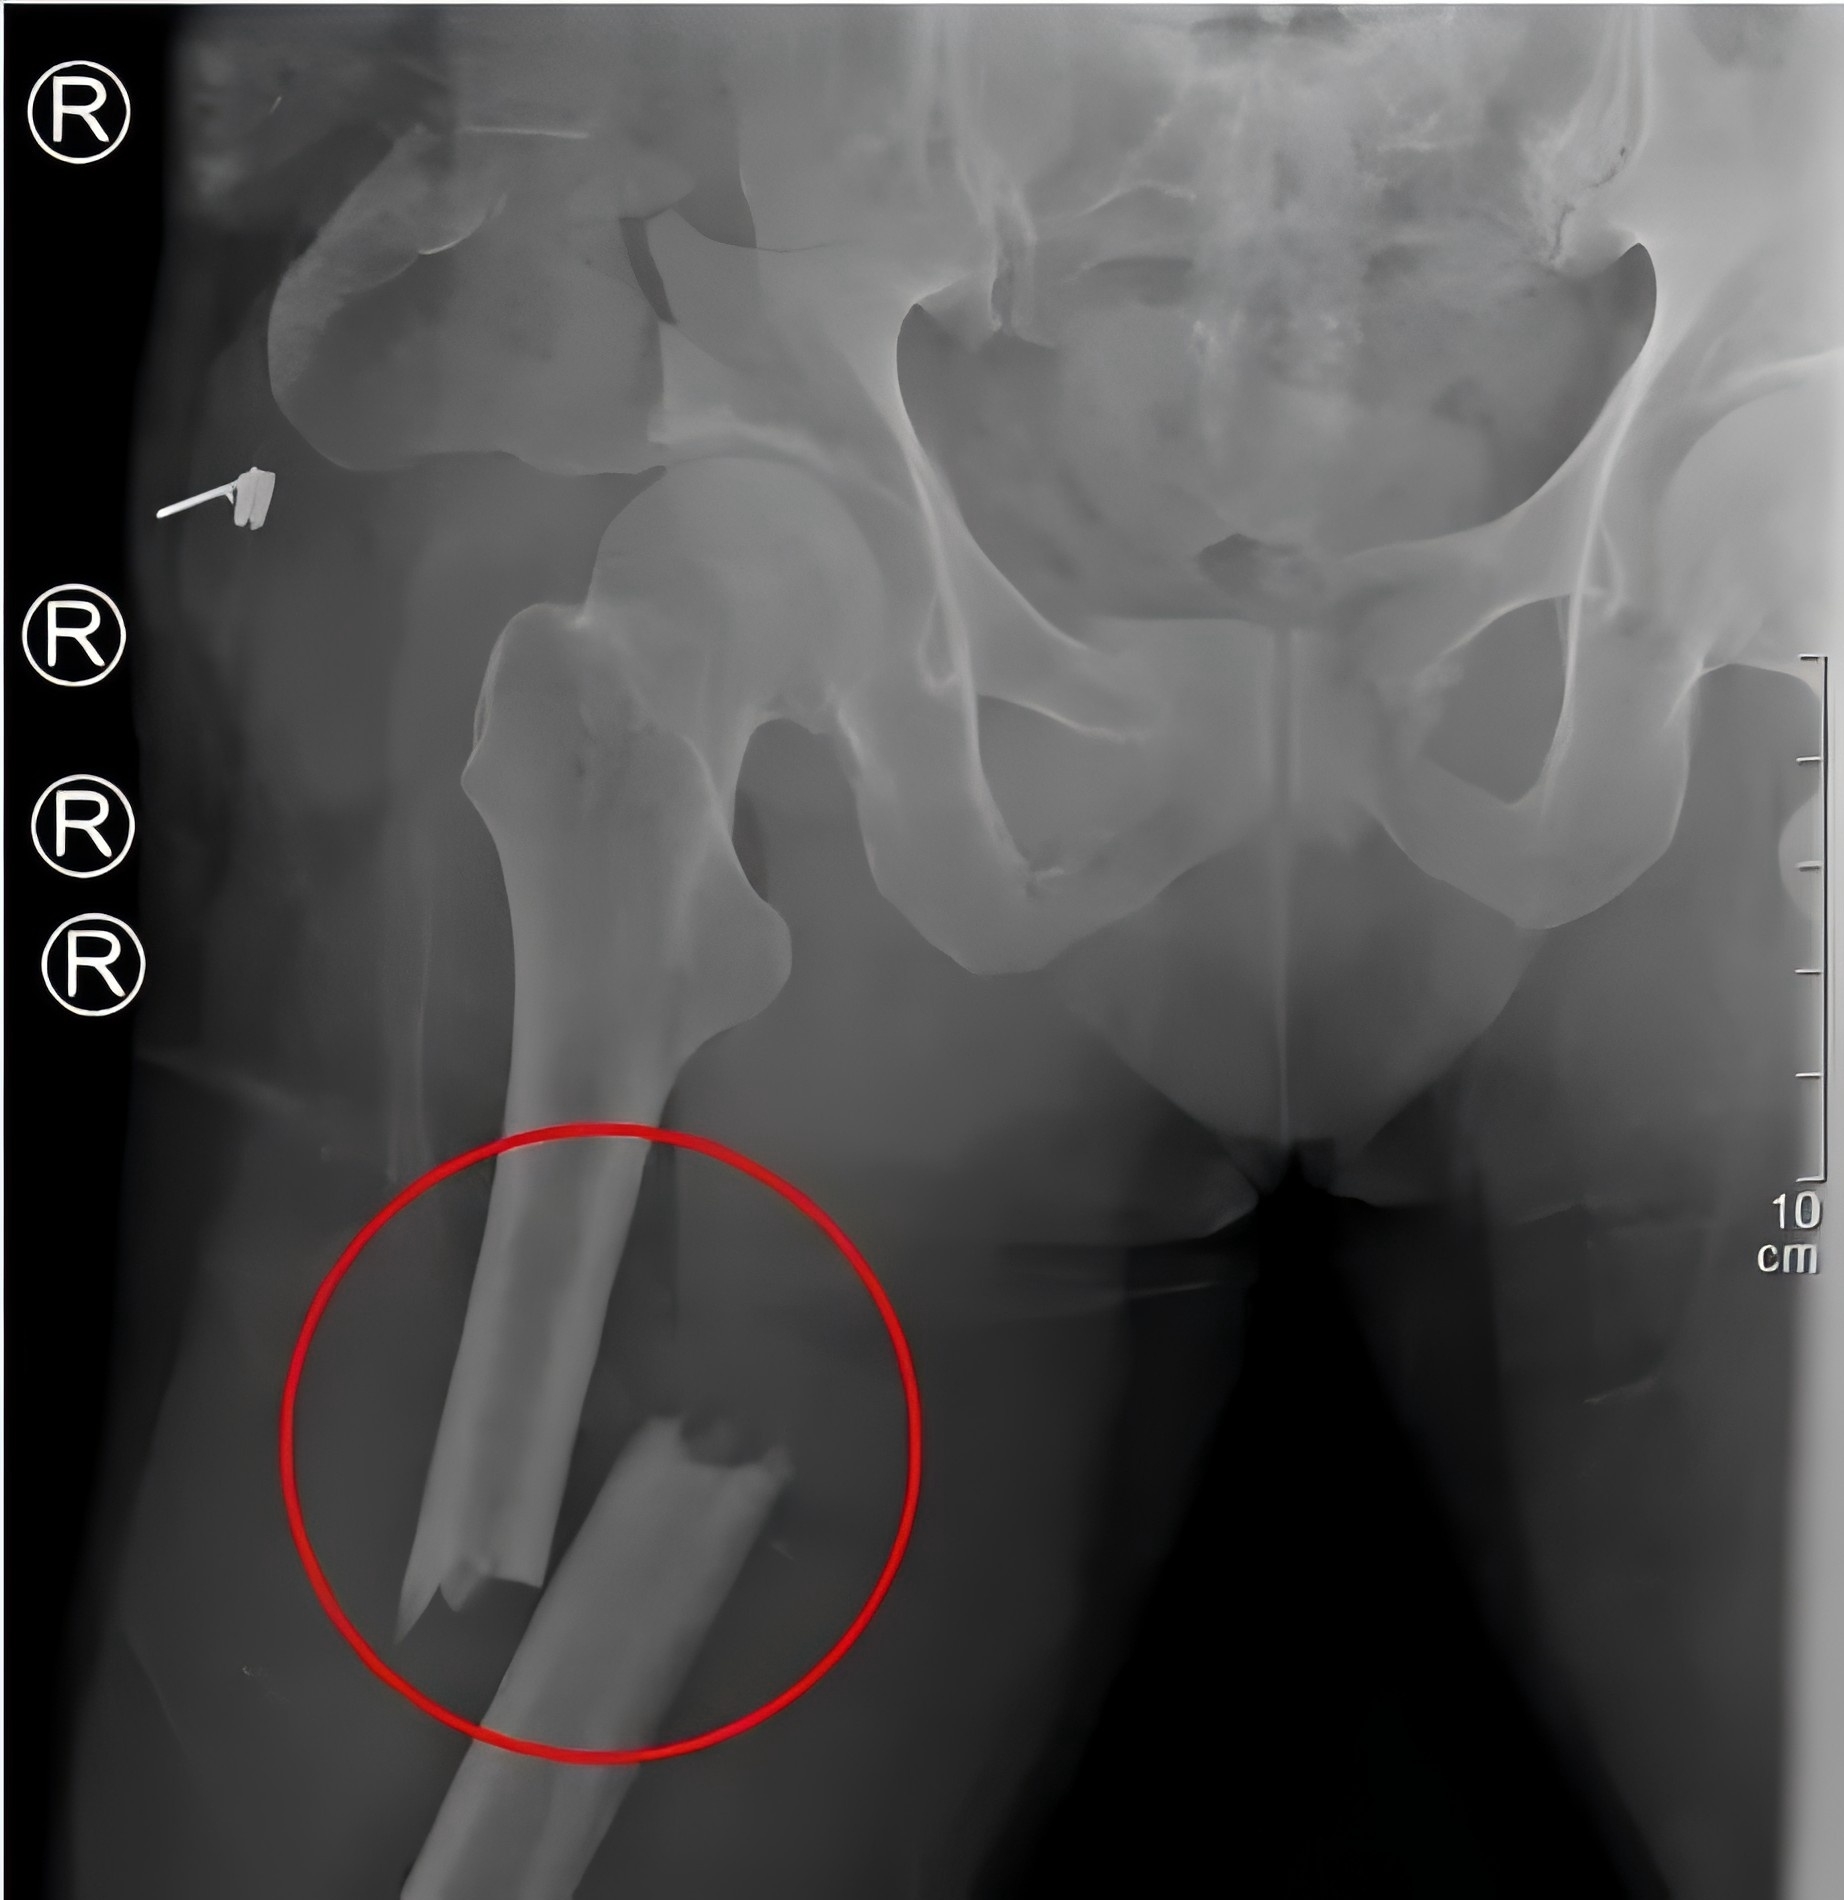

2月28日,48歲的戴某不慎被重物(重量約為2噸)砸傷,導致多發性骨盆骨折、右側粉碎性髂骨骨折、雙側股骨骨折、右側腓骨骨折等多處損傷,尤其是骨盆處幾乎“散架”,患者失血性休克,生命垂危。

殷小軍團隊基于損傷控制理念,為患者量身定制了微創手術方案。手術分為兩期進行:待患者生命體征穩定后,一期先行骨盆及一側股骨骨折微創內固定治療;二期行另一側股骨骨折微創內固定手術。

(患者術后X片)